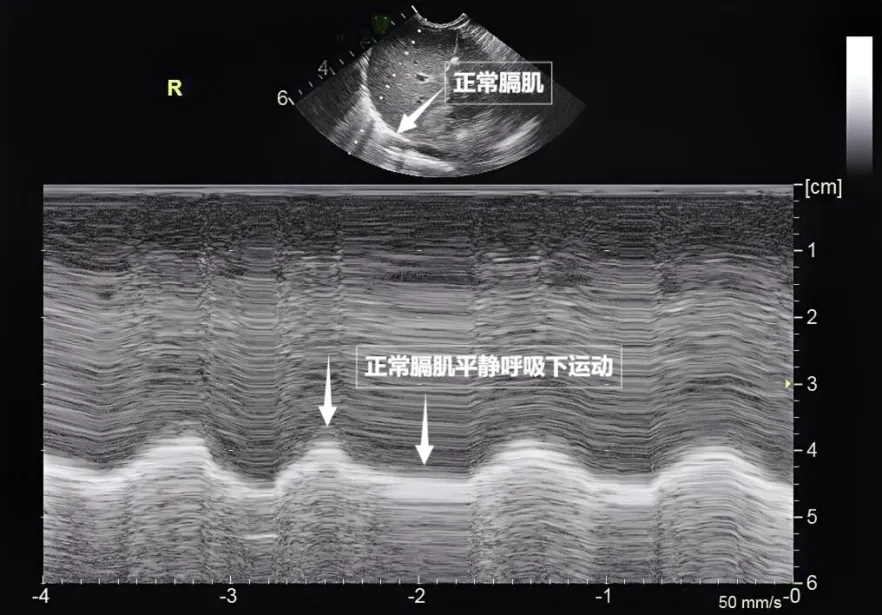

第三景:“呼吸的动力泵”的协同作战——呼吸肌肉

呼吸看似简单,实则是多组肌肉精密配合的“团体操”。肺部超声不仅能观察肺的形态,更能通过实时动态影像,“捕捉”这些呼吸肌的活动状态,为评估呼吸功能提供独特视角。膈肌是呼吸肌的“总指挥”,位于胸腔与腹腔之间。平静呼吸时,膈肌收缩下沉,胸腔容积扩大,空气自然吸入;舒张时,膈肌回升,肺部弹性回缩完成呼气。超声下可见膈肌呈光滑弧形,随呼吸规律上下移动(见下图)。肋间外肌则是“肋间隙的升降机”,收缩时上提肋骨,扩大胸腔前后径,辅助吸气。这对“黄金搭档”承担了日常呼吸70%以上的工作量,是维持呼吸的“主力军”。

图为正常膈肌超声表现。